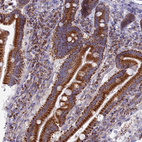

Immunohistochemistry analysis in human duodenum and tonsil tissues using HPA041746 antibody. Corresponding ECI1 RNA-seq data are presented for the same tissues.